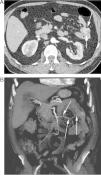

Sangrado digestivo en un paciente durante el postoperatorio de un bypass en la extremidad inferior. A) Corte axial de TC que muestra una ulceración en un asa de yeyuno con sangrado activo en el nicho ulceroso (flecha) e intraluminal. B) La reconstrucción coronal en MIP demuestra el sangrado a nivel de la úlcera (flecha). C) La reconstrucción en fase venosa, más tardía, evidencia una mayor acúmulo de contraste extravasado y mejor delimitación del patrón mucoso del yeyuno (flechas). El ulcus fue tratado mediante enteroscopia con colocación de hemoclip y argón. La biopsia mostró una infección por citomegalovirus.